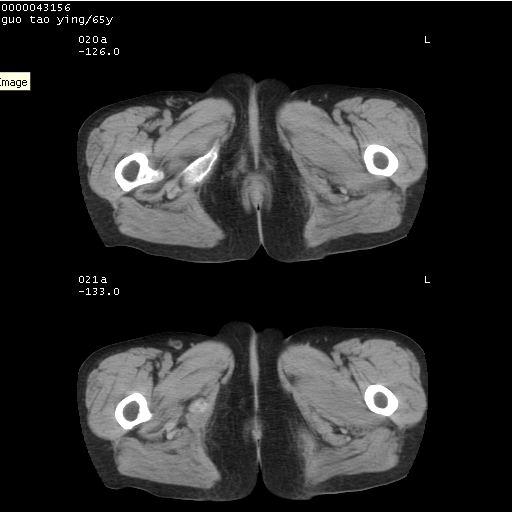

以下是引用黑白光影在2008-1-30 13:22:00的发言:[br]支持左耻骨骨折。[br]未见骶骨骨质明确破坏改变。[br]经楼主提示(勿局限于外伤)。考虑为右侧腹股沟直疝。[br][br][br][br]